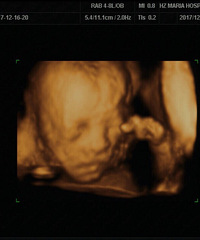

买了根高档验孕棒一测就准

怎么说呢,TA就这么来了从10月开始就处于备用状态因为本身大姨妈就不太正常,自己又比较马虎,过一个星期就会用验孕棒检查一下我们婚期是11月25日,22号准备回家结婚那天检查了一下还是一道杠。想想自己应该就是没怀上,就大大咧咧的回家结婚了。折腾了几天,26号回了嘉兴。27号想